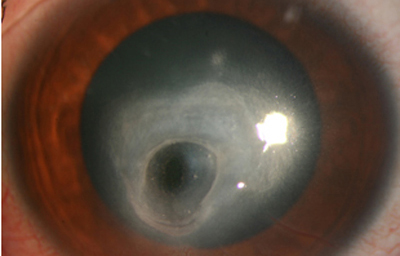

Superficie corneal irregular y grisácea, (Fig. 1, 2) con opácidades granulares en parche y formación de líneas epiteliales elevadas de aspecto granular (Fig. 3), que pueden arborizar dando imágenes de pseudodendritas. Opacidades superficiales satélites. (Figura 4) Inyección ciliar. Ulceración epitelial variante. (Figura 5).

Acanthamoeba Líneas epiteliales elevadas. Síntomas de 40 días evolución

Fig. 3 Líneas epiteliales elevadas. Síntomas de 40 días evolución